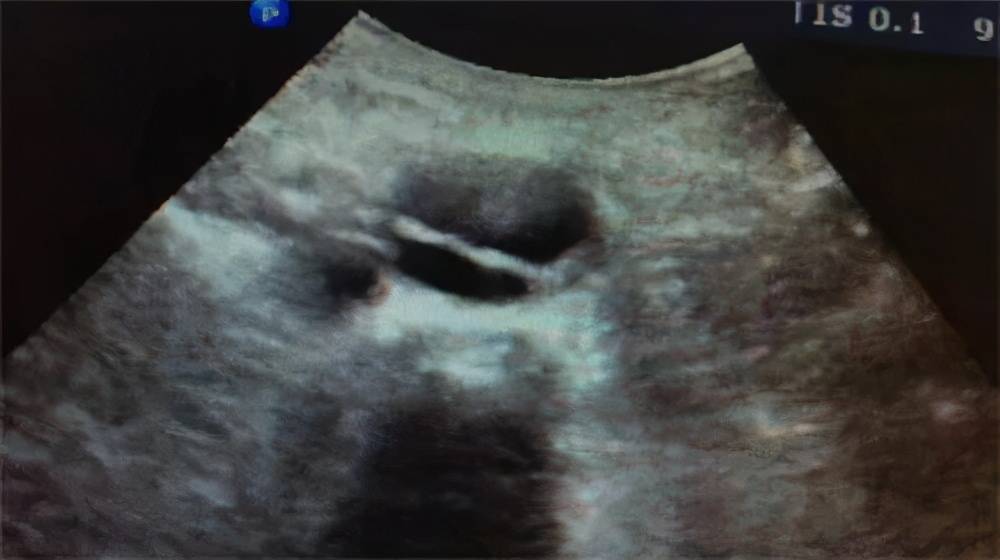

腹主动脉长轴切面 , 腔内局部可见膜样强回声 。 夹层动脉瘤内可见真腔和假腔 , 真假腔的鉴别要注意几点:

腹主动脉长轴切面 , 腔内可见膜样强回声 , 呈双腔征 。

真腔血流通畅 , 血流速度较快 , 血流颜色较鲜艳明亮 , 血流方向收缩期呈正向血流;假腔因前方受阻而血流缓慢 , 血流颜色偏暗淡 , 收缩期正向血流减少或呈反向血流;真腔因流速较快不易形成血栓 , 假腔因流速缓慢而容易发现附壁血栓 。 主动脉夹层的自然经过十分凶险 , 如果未能及时诊断治疗 , 病死率极高 。